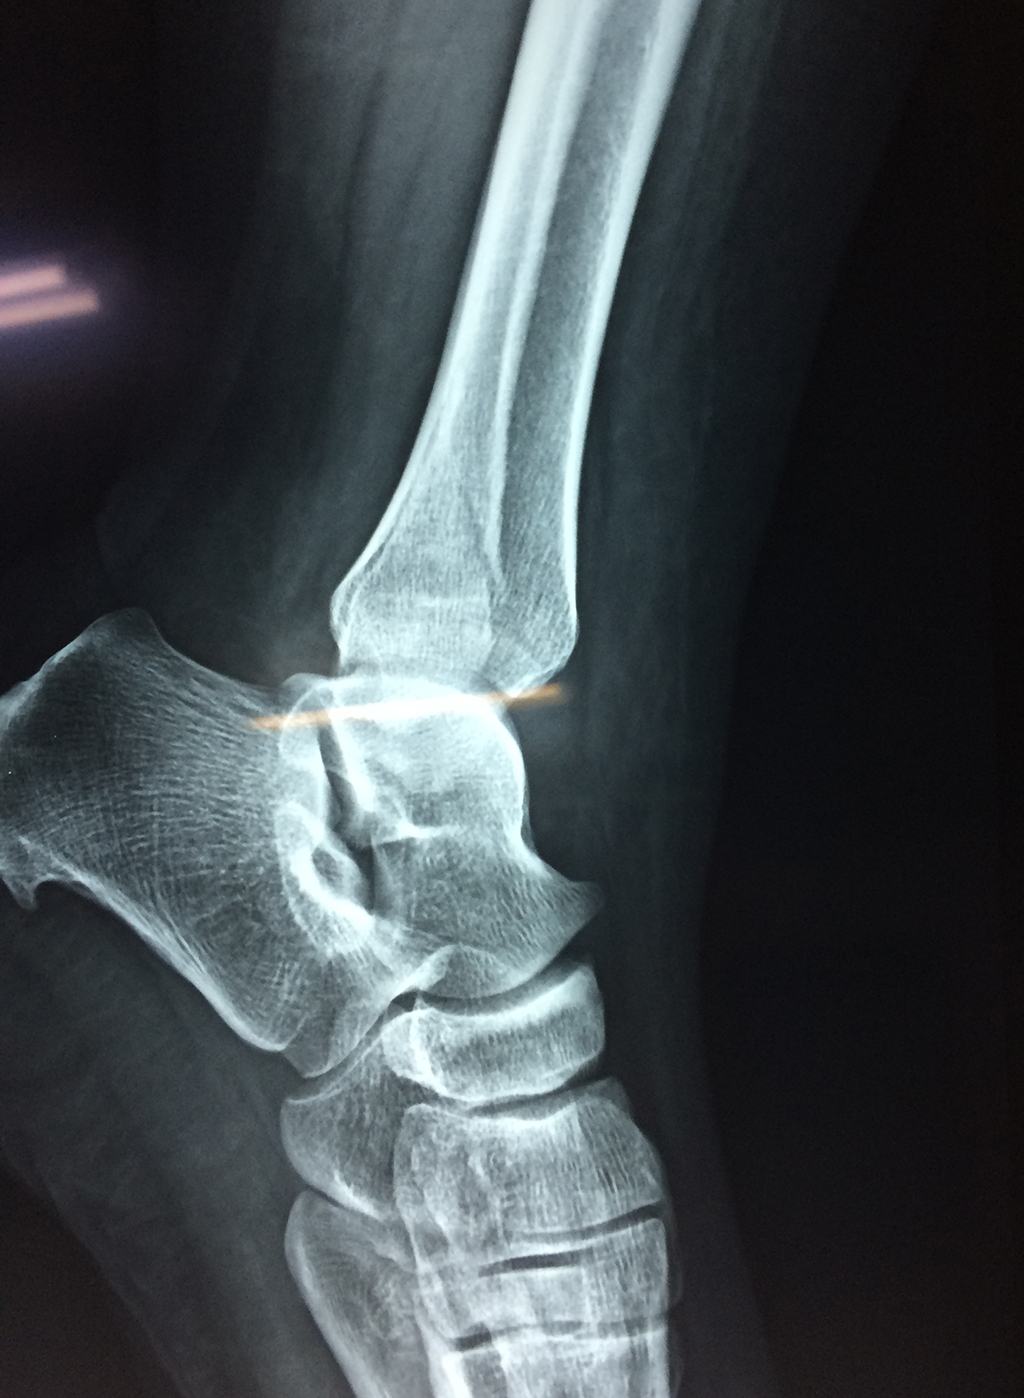

Una fractura de tobillo es la rotura de uno o más de los huesos del tobillo. Estas fracturas pueden ser:

- La fractura se extiende hasta la articulación del tobillo (fractura intra-articular).